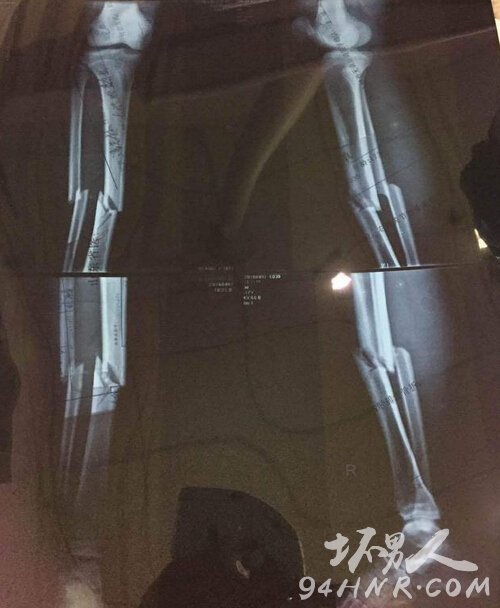

X光显示腿部骨折

4月7日讯 暴力犯规向来是绿茵场上的毒瘤,不但对球员的职业生涯造成影响,还会造成球员严重的身心伤害。全国U17青少年男子足球联赛第一阶段(山东潍坊赛区)的赛事,广西北海同上海申花队的较量,便出现了悲剧的一幕。这场比赛里,一名申花后卫的凶狠飞铲,造成北海球员的双腿骨折,胫腓骨粉碎。